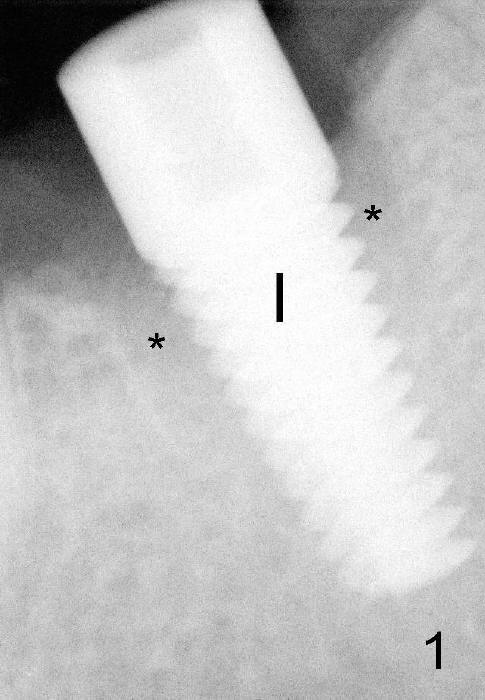

A gingiva-level implant (Fig.1 I) is placed immediately in the extraction site of the tooth #30 (*: remaining mesial and distal sockets after implantation). There appears to be no bone growth in the sockets 4 month postop (Fig.2), although the implant is stable. Clinically there is sign of infection (Fig.3 <) distobuccal to the implant (I). Since the patient is asymptomatic, it feels that the infection may resolve by itself. The abutment (A) is placed and impression is taken. Fourteen days later, the infection remains (Fig.4) after seating the permanent crown.

The infection may be related to chronic infection at the tooth #9. The latter is extracted, but the infection at the site of #30 does not resolve (Fig.5,6). The buccal flap is raised to reveal granulation tissue distobuccal to the implant (Fig.7). Bony defect and implant thread exposure are shown after debridement (Fig.8). Irradiated cancellous bone graft is placed to the defect (Fig. 9, Rocky Mountain Tissue Bank). The flap is closed with relative tension free. The definitive crown is temporarily cemented. The graft is exposed with no infection 2 week post grafting (Fig.10). The distobuccal defect appears to have healed 5 months post grafting (Fig.11) and the crown is permanently cemented (Fig.12). There is no buccal bone resorption, probably associated with immediate implantation. The patient remains asymptomatic 13 months postop.